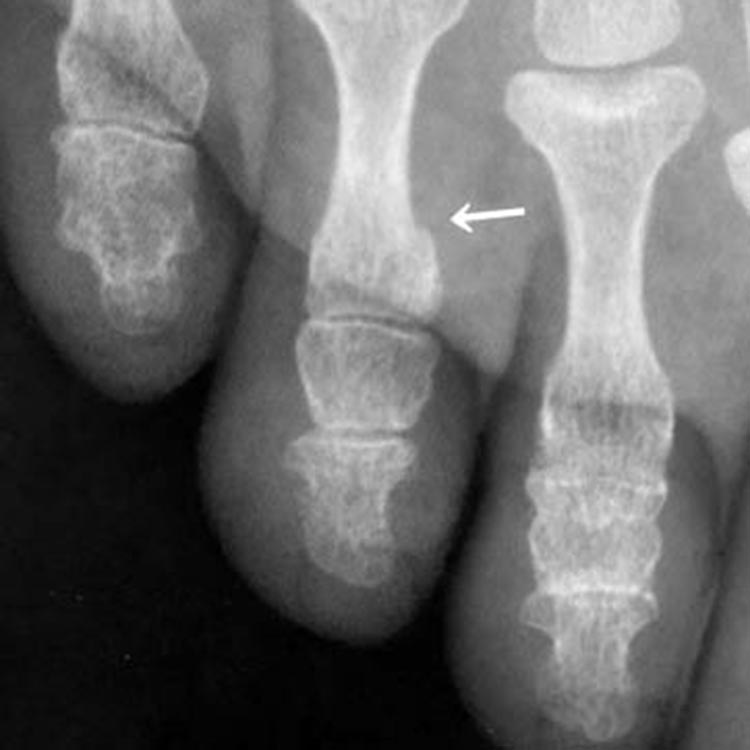

受傷2週後のレントゲン写真

受傷2週後(矢印が新しい骨ができ始めました)